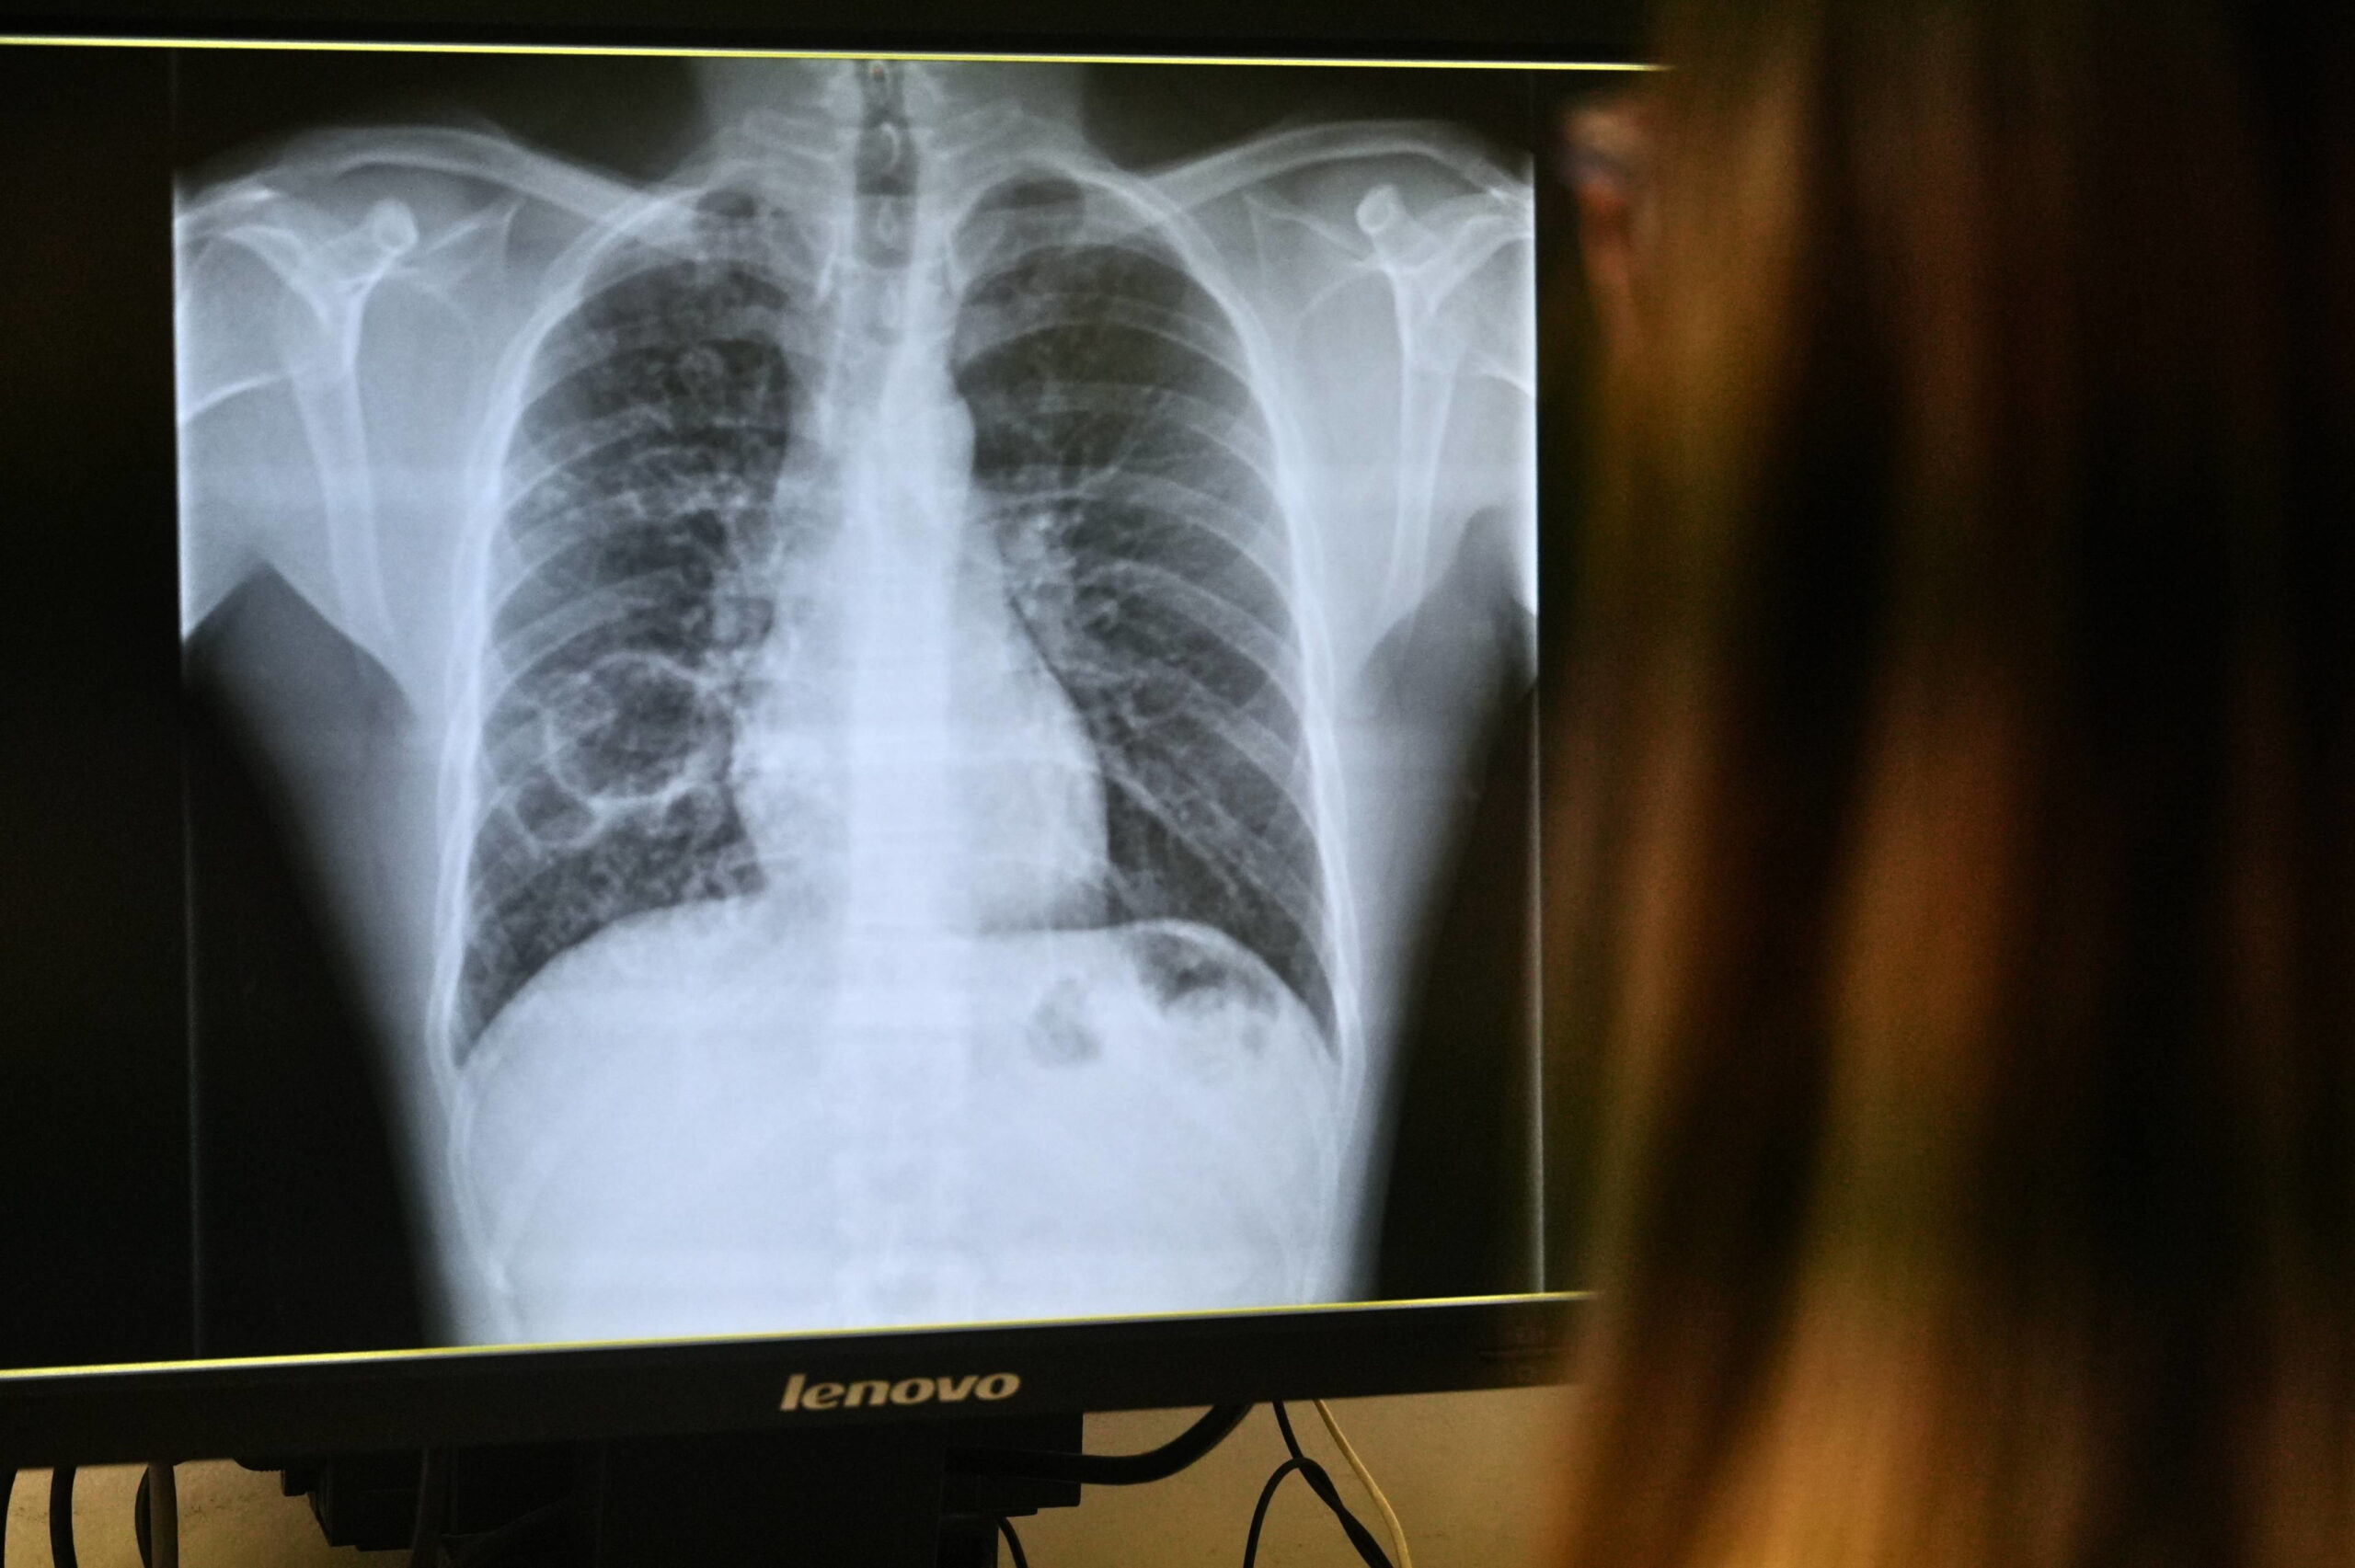

ACN Tarragona – Els ingressos per tuberculosi han augmentat lleugerament a l’Hospital Joan XXIII de Tarragona en els últims anys. Dels nou de 2022, s’ha passat a catorze el 2024 i a setze el 2025. El centre hospitalari ha creat una consulta específica per al control d’aquesta malaltia infecciosa. L’objectiu és millorar l’estandardització dels protocols, intensificar el control de l’adherència al tractament i reforçar la coordinació amb Salut Pública i el Servei de Pneumologia per a fer seguiment i estudi als contactes dels malalts. La incidència de la tuberculosi al Camp de Tarragona se situa en 14,2 casos per 100.000 habitants, segons les últimes dades de Salut, de 2024. La taxa està per sota d’altres territoris amb gran densitat poblacional.

La tuberculosi és una infecció causada per un bacteri que es transmet per via aèria, però no totes les persones que contrauen la infecció arriben a presentar la malaltia. Segons l’Organització Mundial de la Salut (OMS) entre un 5 % i un 10 % dels contagiats la desenvolupen, sovint “coincidint amb una disminució de les defenses”. La malaltia és de declaració obligatòria i té tractament, però si no es fa bé, poden aparèixer “resistències” a la malaltia. Aproximadament un 5% dels casos presenten resistències als fàrmacs habituals.

Els ingressos per afeccions pulmonars a l’Hospital Joan XXIII es fan en règim d’aïllament fins que els pacients no són contagiosos, després de dues o tres setmanes de tractament eficaç.